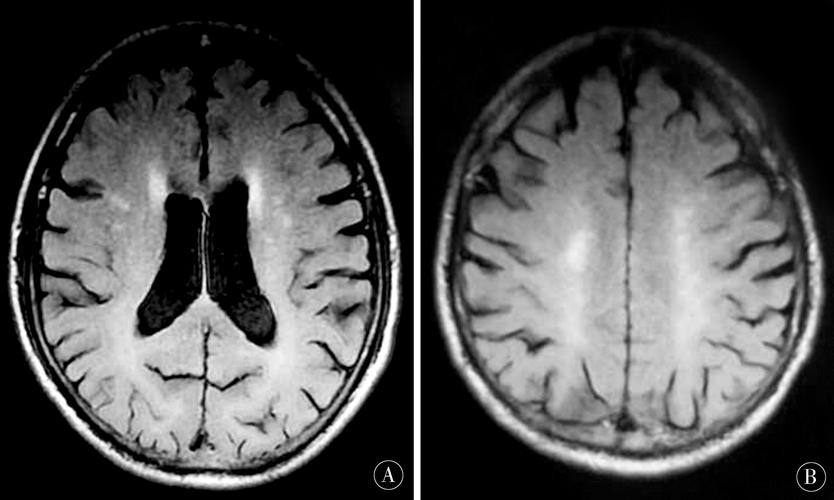

慢性期(> 4周)

这是最终的形态和信号。

(图片来源网络,侵删)

- DWI/ADC:信号通常恢复正常,呈等信号。

- T2/FLAIR:病灶持续呈高信号,代表胶质增生和囊腔形成。

- T1加权像:病灶最终形成边界清晰的低信号(脑脊液样信号),即“腔隙”(Lacune),这是“腔隙性脑梗死”名称的由来。

- 磁敏感加权成像:如果梗死灶内有微量出血,SWI上可能会看到微小的低信号影(含铁血黄素沉积)。